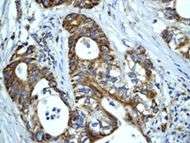

Relationship to cancer

Human Hsp60, the product of the HSPD1 gene, is a Group I mitochondrial chaperonin, phylogenetically related to bacterial GroEL. Recently, the presence of Hsp60 outside the mitochondria and outside the cell, e.g. in circulating blood, has been reported [1], [2]. Although it is assumed that Hsp60 extra-mitochondrial molecule is identical to the mitochondrial one, this has not yet been fully elucidated. Despite the increasing amount of experimental evidences showing Hsp60 outside the cell, it is not yet clear how general this process is and what are the mechanisms responsible for Hsp60 translocation outside the cell. Neither of these questions has been definitively answered, whereas there is some information regarding extracellular Hsp70. This chaperone was also classically regarded as an intracellular protein like Hsp60, but in the last few years considerable evidences showed its pericellular and extracellular residence

HSP60 has been shown to influence apoptosis in tumor cells which seems to be associated with a change in expression levels. There is some inconsistency in that some research shows a positive expression while other research shows a negative expression, and it seems to depend on the type of cancer. There are different hypotheses to explain the effects of positive versus negative expression. Positive expression seems to inhibit “apoptotic and necrotic cell death” while negative expression is thought to play a part “in activation of apoptosis”.[19][20]

As well as influencing apoptosis, HSP60 changes in expression level have been shown to be “useful new biomarkers for diagnostic and prognostic purposes.” [19] According to Lebret et al., a loss of HSP60 expression “indicates a poor prognosis and the risk of developing tumor infiltration” specifically with bladder carcinomas, but that does not necessarily hold true for other types of cancers.[21] For example, ovarian tumors research has shown that over expression is correlated with a better prognosis while a decreased expression is correlated with an aggressive tumor.[21] All this research indicates that it may be possible for HSP60 expression to be used in predicting survival for certain types of cancer and therefore may be able to identify patients who could benefit from certain treatments.[20]